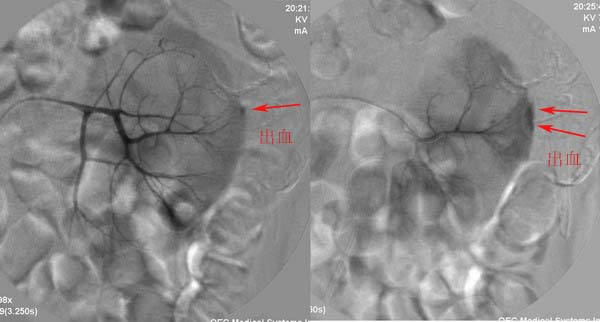

男性,45岁,因左输尿管与肾盂结合部结石住院治疗,经皮肾镜治疗失败后,改做开放手术.手术后3天出现血尿,5天保守治疗仍不能止血,申请肾动脉dsa,见下图片,发帖目的在于请各位分析判断出血部位.

介入治疗过程:

出血超过0.5ml/秒,dsa就应该有阳性征象.